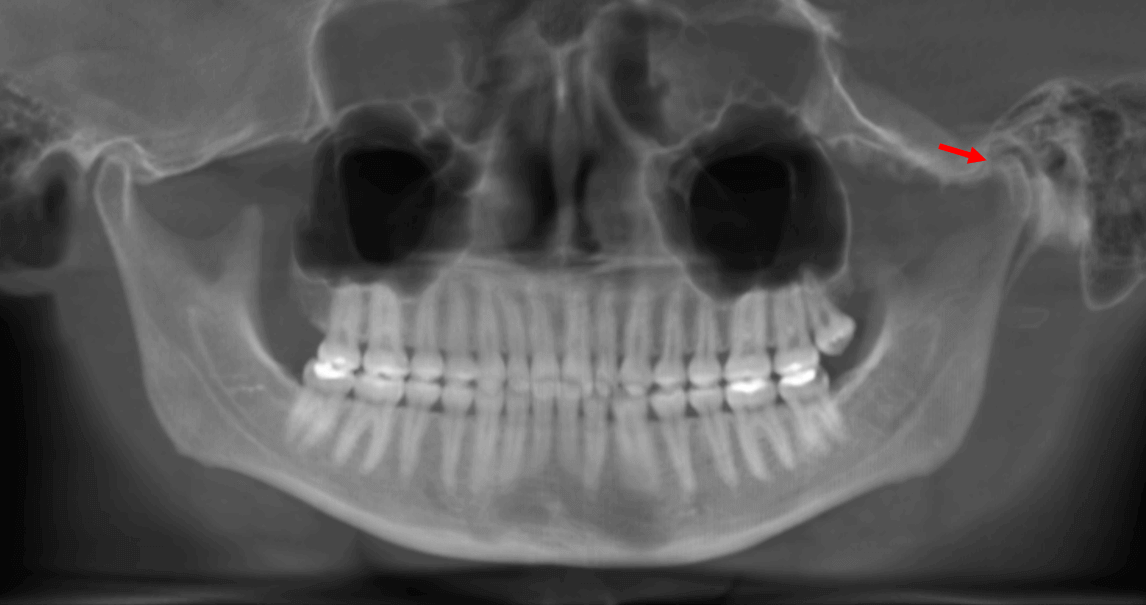

Fig.1

En la evaluación con tomografía computarizad cone beam, se observa la reconstrucción panorámica de ambos maxilares (Fig.1) la ausencia del tercer molar superior derecho y la ausencia de los terceros molares inferiores. La paciente refiere sintomatología articular en la ATM izquierda subsecuente a la extracción de ambos terceros molares inferiores aproximadamente hace 9 años.